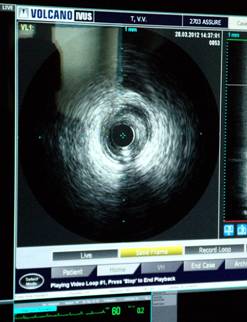

Внутрисосудистое ультразвуковое исследование коронарных артерий- используется для уточнения состояния коронарного русла на диагностическом этапе.

Точная количественная оценка и детальный качественный анализ состояния коронарных артерий, осуществляемые с помощью внутрисосудистого ультразвукового метода, позволяют оценить степень атеросклеротического поражения и выбрать наиболее оптимальный метод лечения.

В настоящее время ВСУЗИ - это один из методов визуализации, который в реальном масштабе времени дает возможность провести тонкий структурный анализ атеросклеротически измененного участка артерии, определить гемодинамическую значимость стеноза, выявить осложненные и структурно нестабильные бляшки. Данный метод помогает в сложных диагностических ситуациях, когда по данным селективной коронарографии не удается ответить на все вопросы, касающиеся патологии венечного русла и гистологической структуры бляшки.